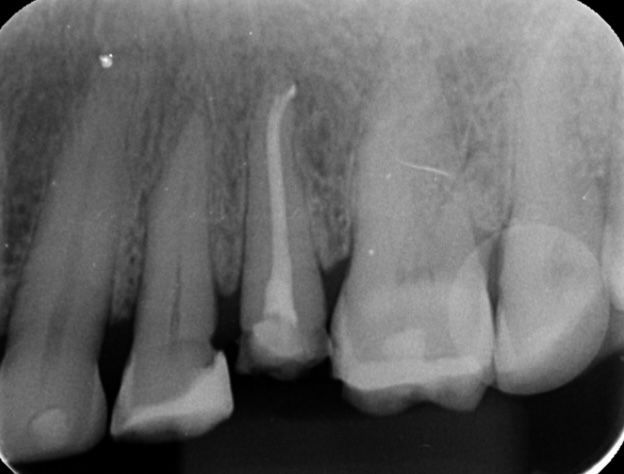

Alguns casos de sucesso